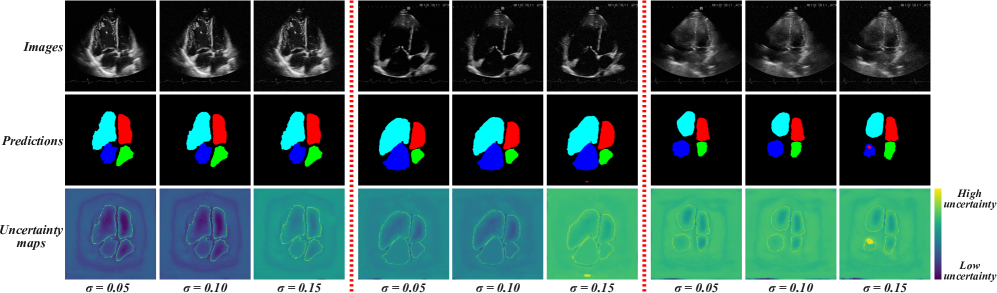

Refer to caption

Figure 6: Visualization of comparison experimental results on the EchoNet dataset. The Scribble column represents scribble annotations, while the Full label column indicates full dense annotations. In scribble annotations, the yellow area represents unlabeled area. In full labels, the green area denotes the ground truth. In other segmentation results, green area indicates accurate segmentation, i.e., the overlap between the segmentation result and the ground truth. Red area represents under-segmentation (false negatives), while blue area indicate over-segmentation (false positives).

All segmentation results are visualized in Figure 6. Six sets of echocardiographic images of the left ventricle with varying sizes were selected, and arranged from top to bottom in ascending order of scale. The green arrows in the figure pointed out the regions where segmentation errors were apparent. As can be seen from the figure, some methods tended to be aggressive in segmentation, especially when dealing with small left ventricles. In the case of large-sized left ventricles, methods like USTM and DMPLS displayed a pronounced tendency towards conservative segmentation, significantly compromising the precision of the anatomical delineation achieved. This suggests that these methods had an insufficient capture of global information. Among the two methods, ScribFormer’s segmented regions notably exhibited a tendency towards aggressiveness in comparison to DMPLS, which we hypothesize may stem from the influence of the Transformer architecture. Nonetheless, they remained insufficient in adequately capturing the morphological characteristics. Furthermore, we notice that some methods failed to segment the region covered by the mitral valve, excluding it from the left ventricle. We speculate that this could be due to the insufficient coverage of scribble annotations in this region, resulting in the model’s inability to capture its features. In summary, our method can overcome most of the above problems and demonstrate advantages in ultrasonic data.